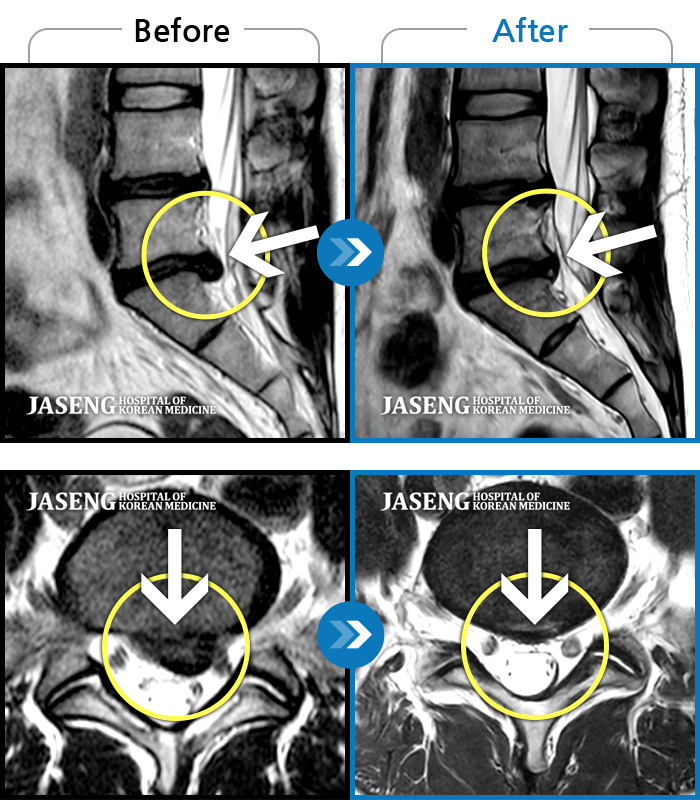

MRI 치료사례

허리디스크

도움받은 사례

강남 · 이남우 원장

허리 통증과 함께 발끝 저림이 1년 이상 되었으며 최근 1-2개월 사이에 증상이 급격히 심해져 우측 다리 앞 뒤가 당기고 힘이 빠져 본원에 내원함

촬영시기

2023.11.20 ~ 2024.08.12